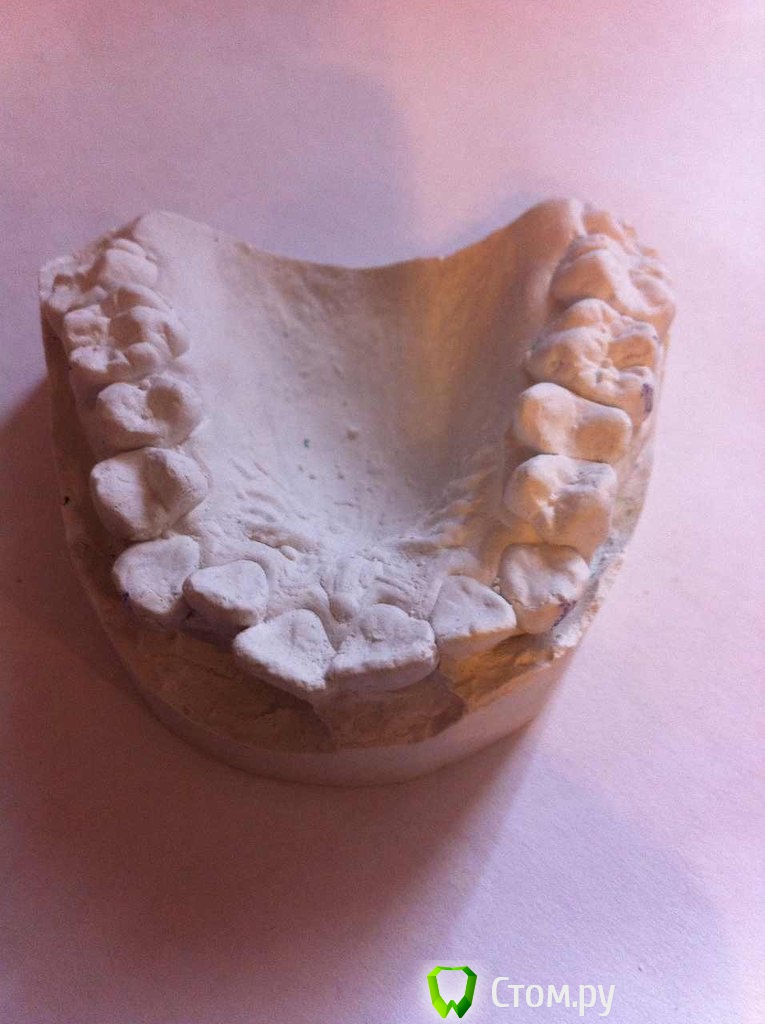

IgorH Опубликовано 7 апреля, 2014 Поделиться Опубликовано 7 апреля, 2014 Добрый деньИнтресует Ваше мнение по поводу необходимости удаления премоляров по моим расчетам-1 скелетный класс,SNA=80SNB=74ANB=6Ось Y=77SN-MP=46вертикальный тип роста WITS меньше 1 мм поэтому 1 скелетный класс по дуге:на вч дефицит места 11 ммна нч 8 ммуглы резцов к плоскостям челюстейвч 115 нч 102 межрецовый угол 107 согласно треугольникам Фастлайта,для первого класса углы 110/90значит нужно сделать навч 115 ретрузию до 110 на нч 102 ретрузию до 90 итого:дефицит места,протрузия,выпуклый профиль,зубы вне дуги Все говорит о том,что необходимо лечение с удалением 4 зубов,интересует Ваше мнение Заранее Благодарю Ссылка на комментарий

IgorH Опубликовано 9 апреля, 2014 Автор Поделиться Опубликовано 9 апреля, 2014 Благодарю за ответ,щас поищу как тут прикреплять фото,профиль выпуклый,да и дефецит места я бы не сказал что минимальный...если ничего не удалять,то по моим прогнозам,зубы наклоняться в протрузию,а тут и так уже протрузия есть,что ее усугубит,и ухудшит профиль.по поводу жалоб-пациентка доверяет моему мнению,а я хочу как лучше с точки зрения лицевой эстетики,а не только зубные ряды выровнять 1 Ссылка на комментарий

LeFor Опубликовано 17 апреля, 2014 Поделиться Опубликовано 17 апреля, 2014 в моих расчетах на вч дефицит места не 2 мм,а 11 мм,возможно я ошибся,я считал по моделям,мезио-дистальные размеры зубов,и место в зубном ряду с помошью нитки(знаю есть специальные графические методы) .а как Вы просчитываете деффецит места в зубном ряду? на глаз)) у меня же есть только фото... дефицит ну максимум 4мм... максимальная потеря,вы имеете ввиду анкораж? анкораж, на сколько я знаю переводится примерно как- опора... так что я имею ввиду наоборот, закрывать пространства с максимальной потерей опоры. я планирую на вч устанавливать Даемон с высоким торком,для стабилизации фронта или я ничего не понял, или... зачем высокий торк если вы боитесь протрузии? Мне ближе всего лечение с удалением вверху 5,и внизу 46,правда,я еще выбираю,убирать 46 или 45, в любом случае,оставшийся зуб планируем перелечивать,и качественно запломбировать канал только проверьте прежде 47... если там все обойдется, то лучше убрать 46, т.к. 45 лучше выглядит+ больше вероятности что его нормально пролечат+ симметричное лечение предсказуемее.. 1 Ссылка на комментарий